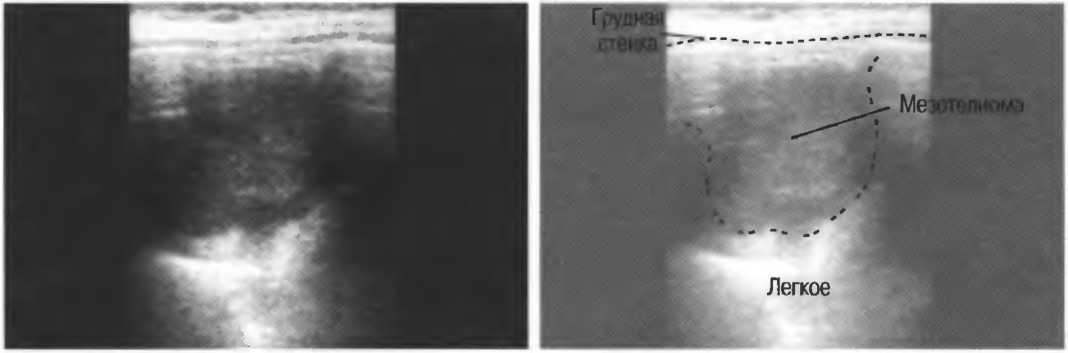

На практике, наиболее значимые в клиническом плане артефакты возникают при проведении биопсии или аспирации под контролем ультразвука. До тех пор пока кончик иглы не появится в плоскости сканирования на экране, он не будет визуализироваться, и может создаться ложное представление о том, что игла значительно короче (рис. 21в).

Рис.21 в. Изображение иглы в емкости с водой. Слева игла находится в плоскости сканирования не полностью, в результате чего выглядит короче, чем есть на самом деле (крестик определяет реальную глубину проникновения иглы). Справа игла визуализируется полностью.